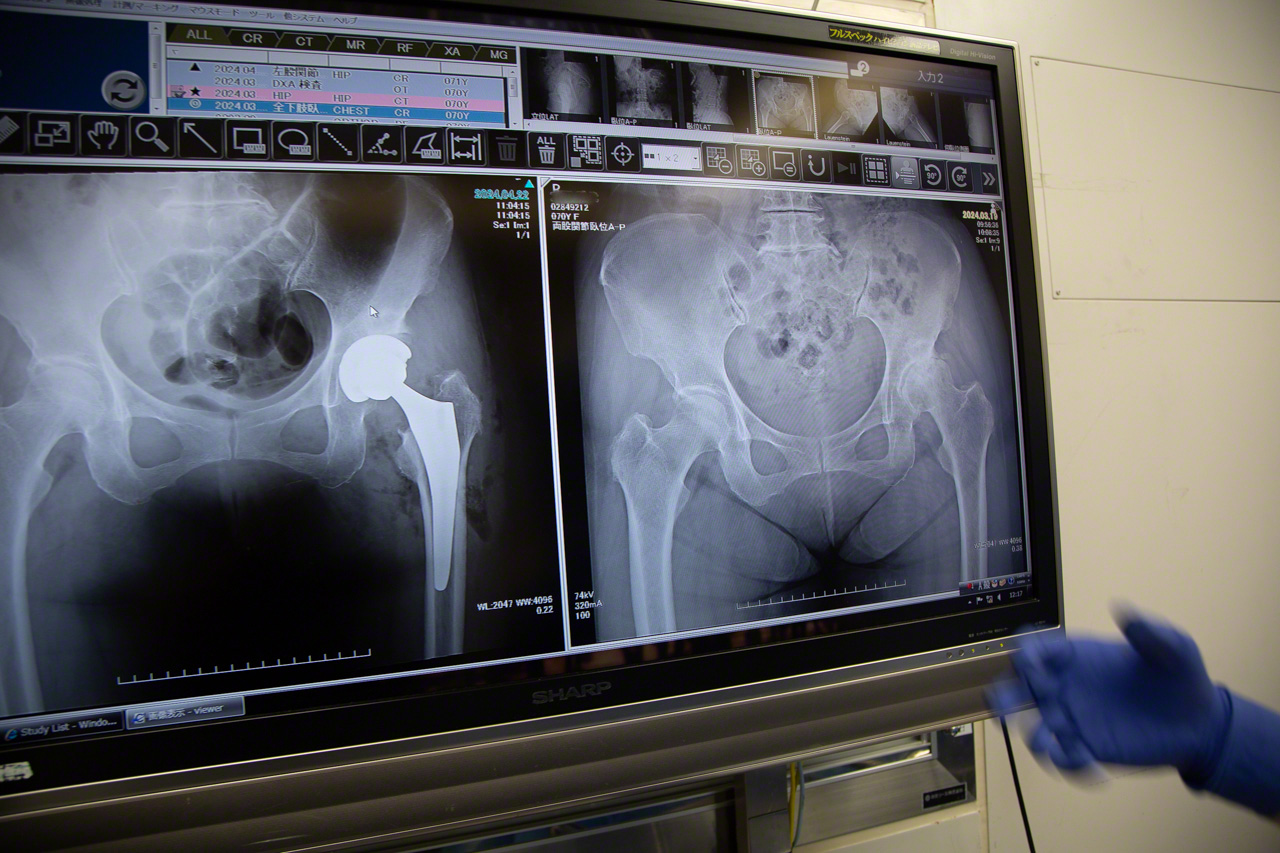

Una semana antes de la operación, los médicos se reúnen en una estancia a la que llaman “la sala de dibujo”. Rodeados de enormes pantallas que muestran pruebas diagnósticas de imagen como radiografías y TAC, debaten minuciosamente sobre los métodos quirúrgicos más adecuados para cada uno de los pacientes a los que van a operar la semana siguiente.

Fotografía del encabezado: Analizando una radiografía de la cadera para planificar la operación.